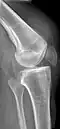

Weitere Bildbeispiele

Riss der Sehne bei Vorschädigung mit Sehnenansatzverkalkungen, die jetzt nach oben gezogen sind